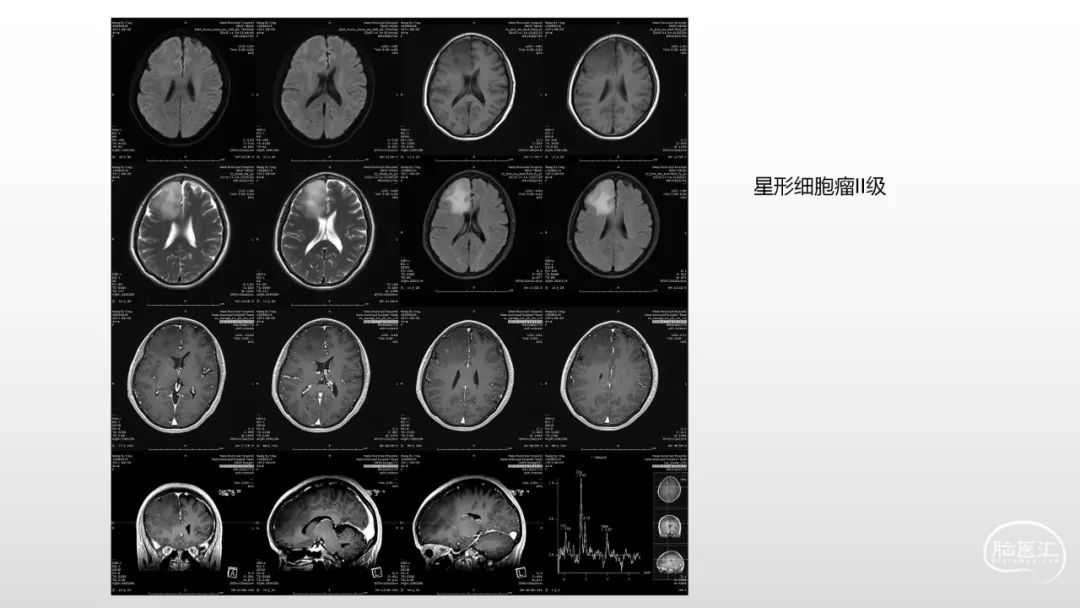

颅脑影像诊断基础知识讲座:感染和免疫性疾病1